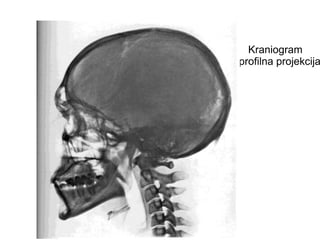

Kraniogram

– profilna projekcija